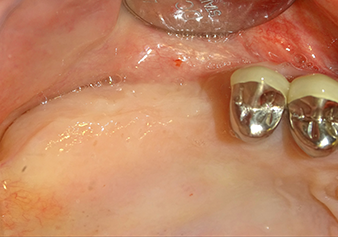

Valutazione preoperatoria: la cresta alveolare è guarita bene, compresa la gengiva sufficientemente ampia e cheratinizzata

Fig.1: Valutazione preoperatoria: la cresta alveolare è guarita bene, compresa la gengiva sufficientemente ampia e cheratinizzata.